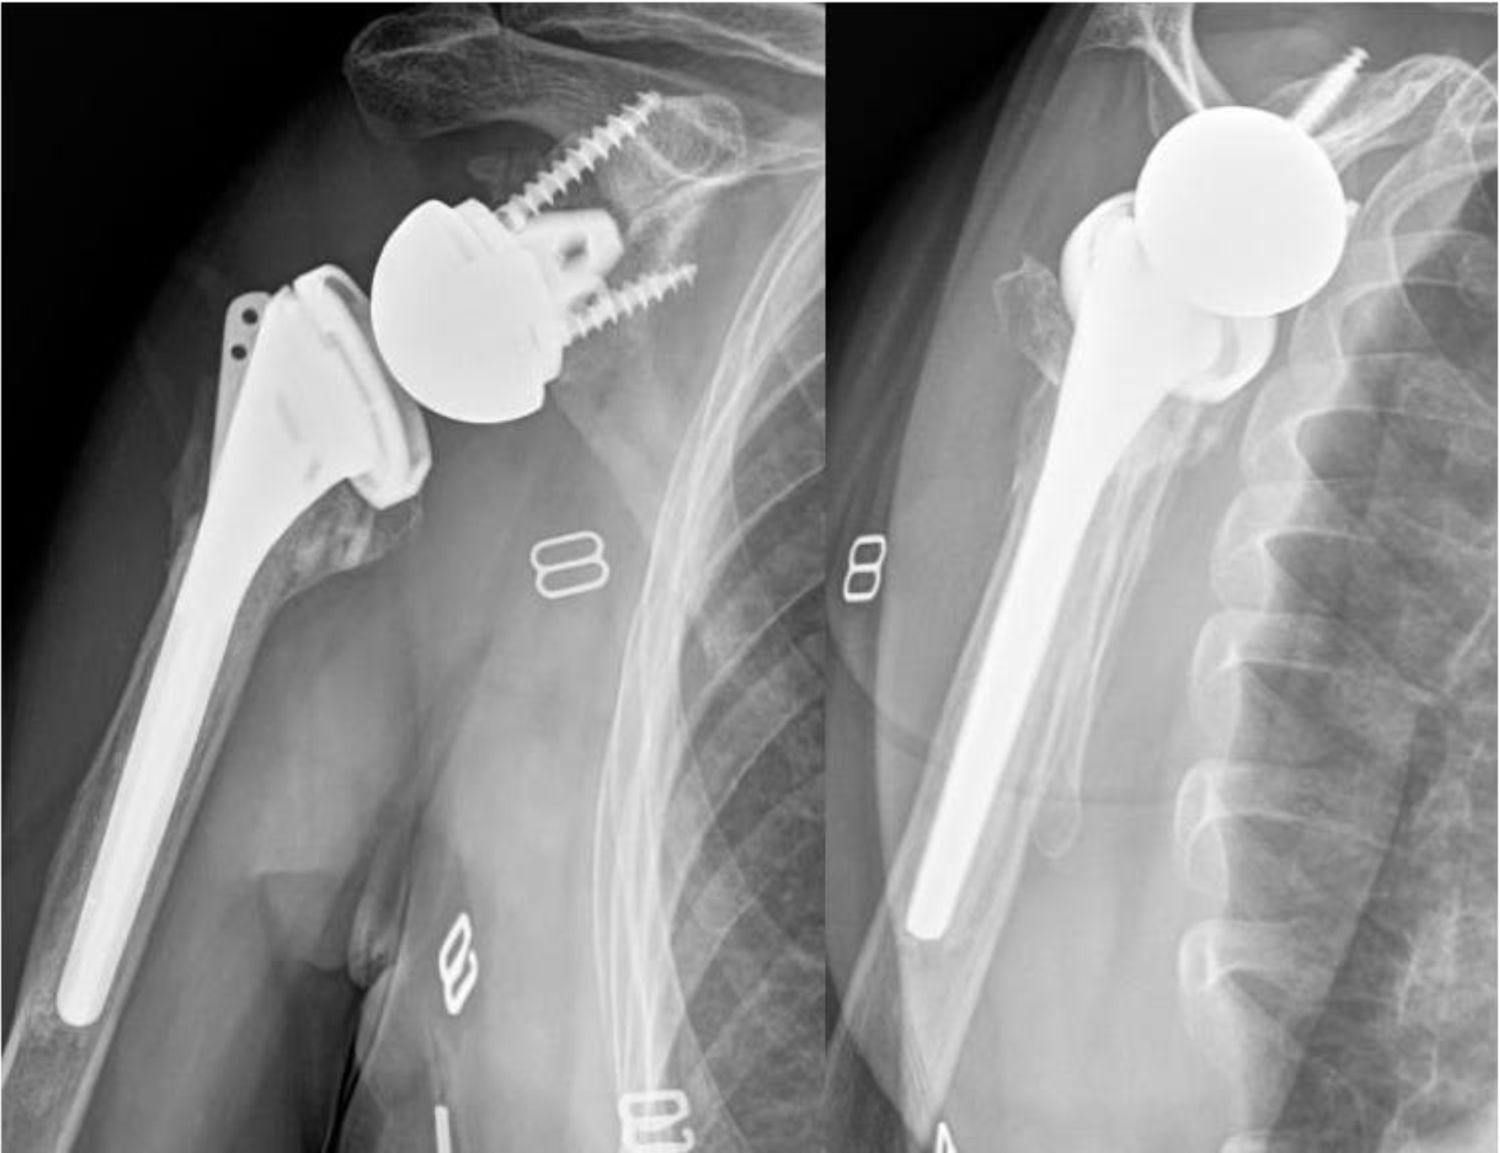

La consolidación anatómica se definió en la radiografía anteroposterior (AP) con rotación neutra, al observar la tuberosidad mayor a nivel de la cara lateral del vástago humeral, en contacto con la diáfisis y sin sobrepasar el extremo superior del polietileno (fig. 2). Se consideró consolidación no anatómica cuando la tuberosidad no era visible en la radiografía de hombro anteroposterior, pero su consolidación se evidenciaba en la radiografía de perfil o axial, indicando una migración o traslación posterosuperior (fig. 3). Finalmente, se determinó como falla de consolidación la presencia de signos radiográficos de seudoartrosis o lisis en la radiografía anteroposterior de hombro y axial de escápula (fig. 4).

ResultadosEn total, se incluyeron 73 pacientes a los que se les realizo una ARH por FHP, con una mayoría de mujeres y una edad media de 76años (rango 65-94). El seguimiento fue mayor en el grupo MAL que en el grupoL: 30,9±12,8 meses versus 17,9±3,4meses, respectivamente. No se observaron diferencias estadísticas significativas entre los grupos en cuanto a edad, sexo, lado afectado ni tipo de fractura (tabla 1). En el análisis radiográfico, la consolidación tuberositaria global se evidenció en 60 (82,2%) de los casos, mientras que 13 pacientes (17,8%) mostraron signos compatibles con fallo de consolidación. El grupoL mostró una tasa de consolidación total significativamente mayor (100%) frente al grupo MAL (75,5%). El grupoL mostró una mayor proporción de consolidación anatómica, mientras que las fallas de consolidación ocurrieron exclusivamente en el grupo MAL. La diferencia en la distribución de los patrones de consolidación entre ambos grupos fue estadísticamente significativa (p=0,020; tabla 2).